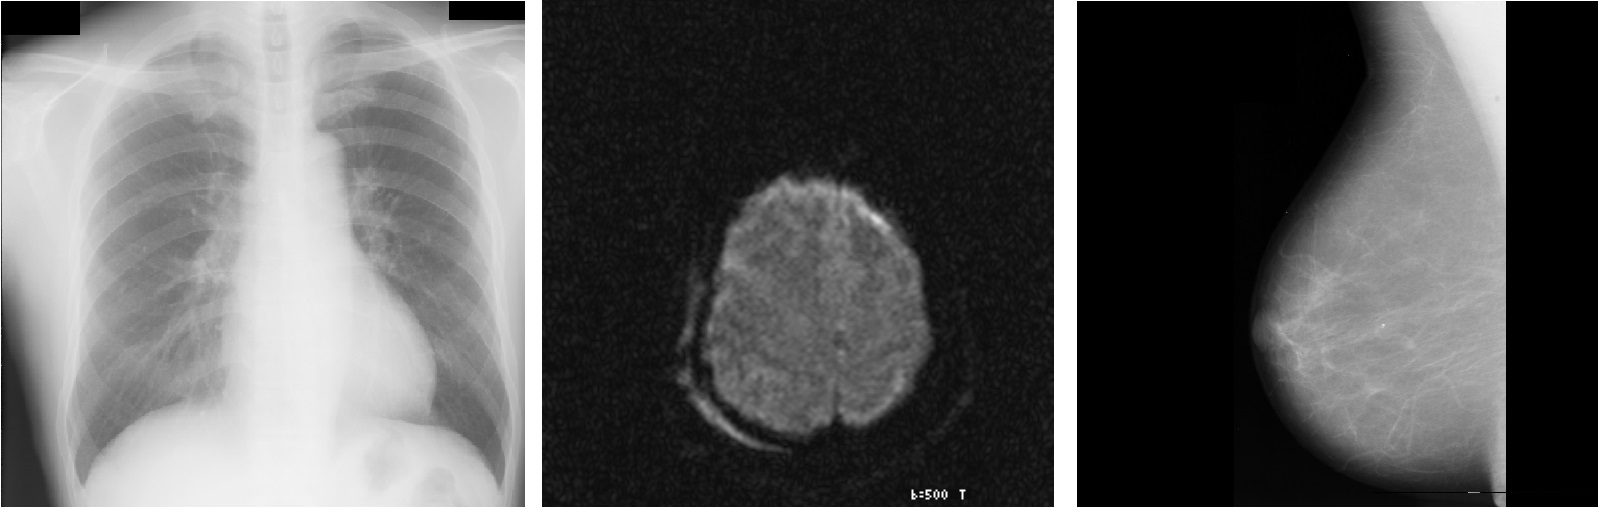

This research addresses the development of multimedia mining projects by applying analytical techniques to texts, images, audio, and video. In order to develop these projects, a methodology to develop multimedia mining projects (Multimedia Analytical Methodology-MAM) is proposed. Likewise, the construction of a software tool (known as Multimedia Analytical Platform-PAM) which allows the analysis of multimedia mining is introduced. Methodology and platform are evaluated with two study cases on prediction of mammography abnormalities and analysis of medical imaging similarity. Results obtained allowed validating the steps proposed in the MAM methodology and using the PAM platform to extract the characteristics of medical images, to apply data mining techniques, and to satisfactorily evaluate the results obtained.